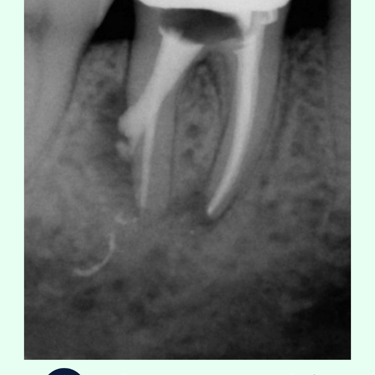

Evaluación Inicial: Examen clínico y radiografías para identificar la perforación y planificar el tratamiento.

Limpieza y Desinfección: Se limpian y desinfectan el conducto radicular y la perforación.

Sellado de la Perforación: La perforación se sella con materiales biocompatibles específicos para endodoncia, como MTA (Agregado de Trióxido Mineral).